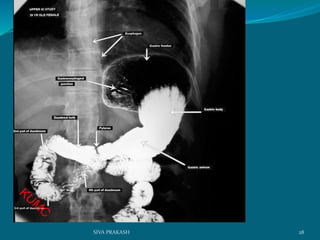

BA Meal follow through:

28SIVA PRAKASH

The pattern of the mucosal lining of the first part of the duodenum is different

from the other parts. longitudinal pattern of the mucosa of the first part of the

duodenum forming what is known as the duodenal cap This pattern is very

similar to that of thepylorus of the stomach This pattern changes to a

more flecked appearence in the distal duodenum